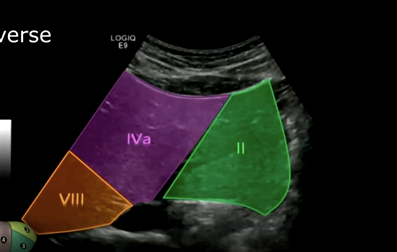

Superior segments of the liver: Segment two, segment four a, and segment eight.

Superior segment of the right lobe (transverse): Hepatic veins, segments four a, eight, and seven.

Middle hepatic vein separates four a from eight.

Right hepatic vein separates eight from segment seven.